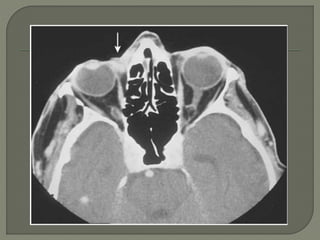

 In the case of carcinomas involving the medial or

lateral canthi of the eyes

 one should consider obtaining either a (CT) or

(MRI) scanto assess the depth of invasion

 because apparently superficial cancers

sometimes extend along the wall of the orbit

CT Scan is done to role out bone and cartilage

invasion

 Lymph node status can also be assessed